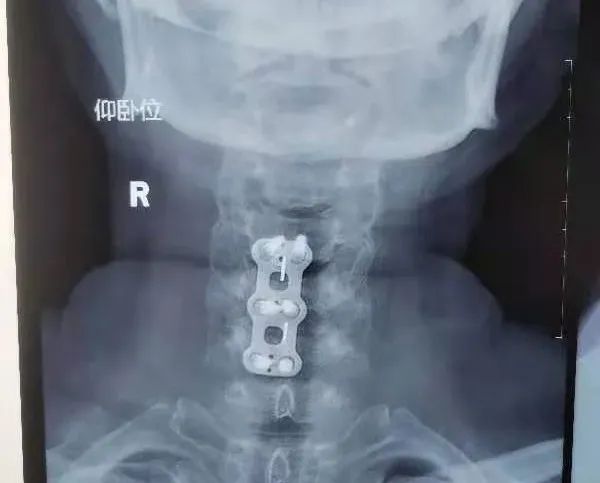

入院查各项化验、检查无手术禁忌,于2022年4月1日在全麻下行颈4-5、5-6椎间盘切除、植骨融合内固定术。

术后第三天复查颈椎正侧位片钉棒位置良好,佩戴颈托下地活动。自诉症状明显减轻,双手麻木基本消失,双下肢活动自如,感觉已基本正常。